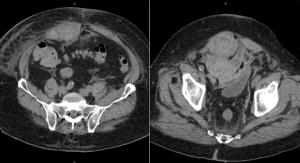

A 30-year-old man who recently underwent induction chemotherapy for bone marrow transplant is admitted with neutropenia and right lower-quadrant abdominal pain. What is your diagnosis?